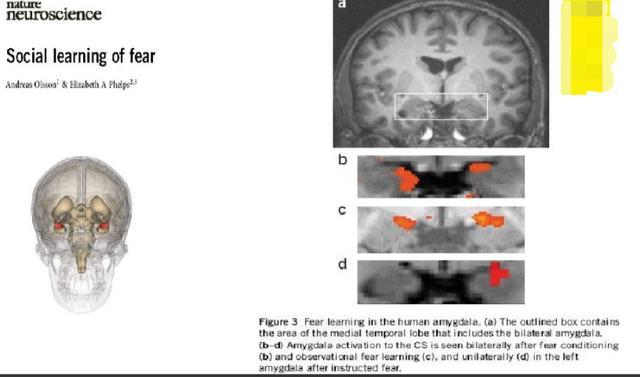

如下这张图,是人类大脑的恐惧中心部位,杏仁核所在的位置,见a图的方框位置。

b,c,d是不同情况下对应大脑的恐惧中心活化的情况。

b图是只要铃声一响,大脑的恐惧中心立即活化,也就是此时,电还没有出来,但是大脑知道电要来了,于是立即恐惧起来。

c图则是看着被电的人的大脑图,恐惧中心也是活化的,也就是看着别人被惩罚,看的人也一样恐惧。

d图则是电左边的手,大脑右边恐惧中心活化。